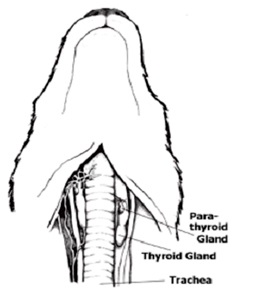

Hyperparathyreosis - egy olyan endokrin betegség jellemző túlzott termelése a mellékpajzsmirigy mirigy, mellékpajzsmirigy-hormon (PTH vagy), amely felelős az egyensúly fenntartása a kalcium és a foszfor a vérben. Ha a vér kalcium szintje csökken, PTH-szekréciót növekszik, ami mosódik kalcium csontból, hogy normalizálja a szintje a vérben és más szövetekben. Mellékpajzsmirigy található a nyakon, közel vagy a pajzsmirigy és a négy lebeny. Hyperparathyreoidismus fordulhat elő, ha egy vagy több prosztata lebeny kezdenek túlzott mennyiségű hormon.